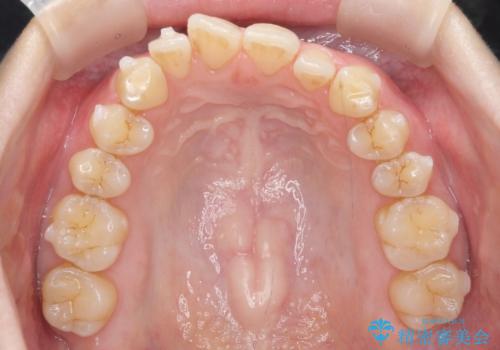

前歯のガタつき インビザラインで 下の前歯を1本抜歯

- 前歯のがたつきを主訴に来院。マウスピース矯正を希望されました。

治療にあたり、下の前歯を一本抜歯しています。

非抜歯で無理に治療をしようとすると、下の前歯の骨が薄く歯ぐきが下がったり、歯がぐらついたり、がたつきが完全にとれないリスクがあることを説明しました。

下の前歯が3本になるため、上下の正中は合わない仕上がりとなりますが、正中を合わせるには上下左右4本抜歯の上、ワイヤー矯正となってしまいます。

それよりは抜歯の数も少なく、メリットが大きいのではないかと説明し、選んでいただきました。

短期間できれいな歯並びになり、大変満足していただきました。